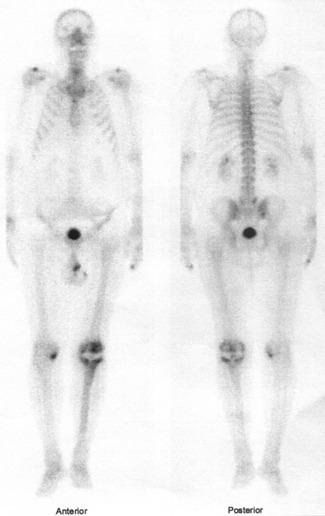

Celotělovou scintigrafii (v přední a zadní projekci) a statické pozdní scintigramy (pozdní kostní fáze) jsme provedli na stejné kameře E.CAM firmy Siemens za 2,5 hod. po aplikaci (statické scintigramy - délka akvizice 5 minut – současně v přední a zadní projekci a další akvizice současně obě boční projekce). Je výrazně zvýšená depozice radiofarmaka opět jak kolem femorální, tak kolem tibiální komponenty TEP. Dále je patrné ložisko zvýšené depozice radioindikátoru v mediálním kondylu pravé

Tedy současně se zvýšenou perfuzí v oblasti celého pravého kolena a v mediálním kondylu pravé tibie je výrazně zvýšená osteoblastická aktivita kolem femorální a tibiální komponenty TEP i v mediálním kondylu pravé tibie

(obr.3, 4).

/ Obr. č. 4: Celotělová scintigrafie skeletu v přední a zadní projekci/